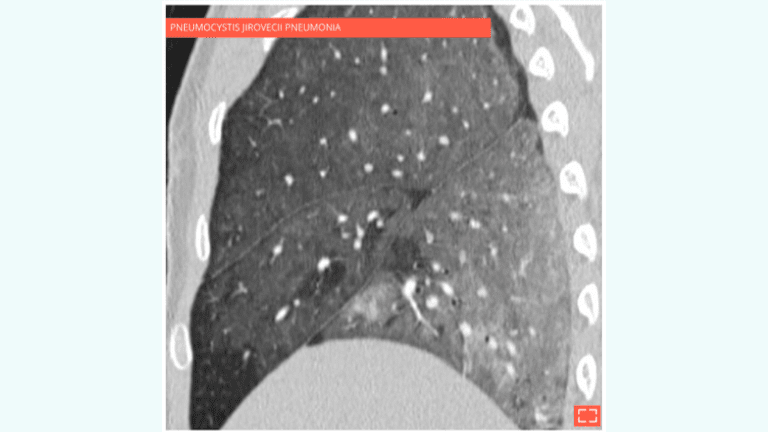

• Pulmonary infection: pneumocystis jirovecii pneumonia, cytomegalovirus (CMV), etc.

Diffuse ground-glass opacity of the lung sparing subpleural areas.